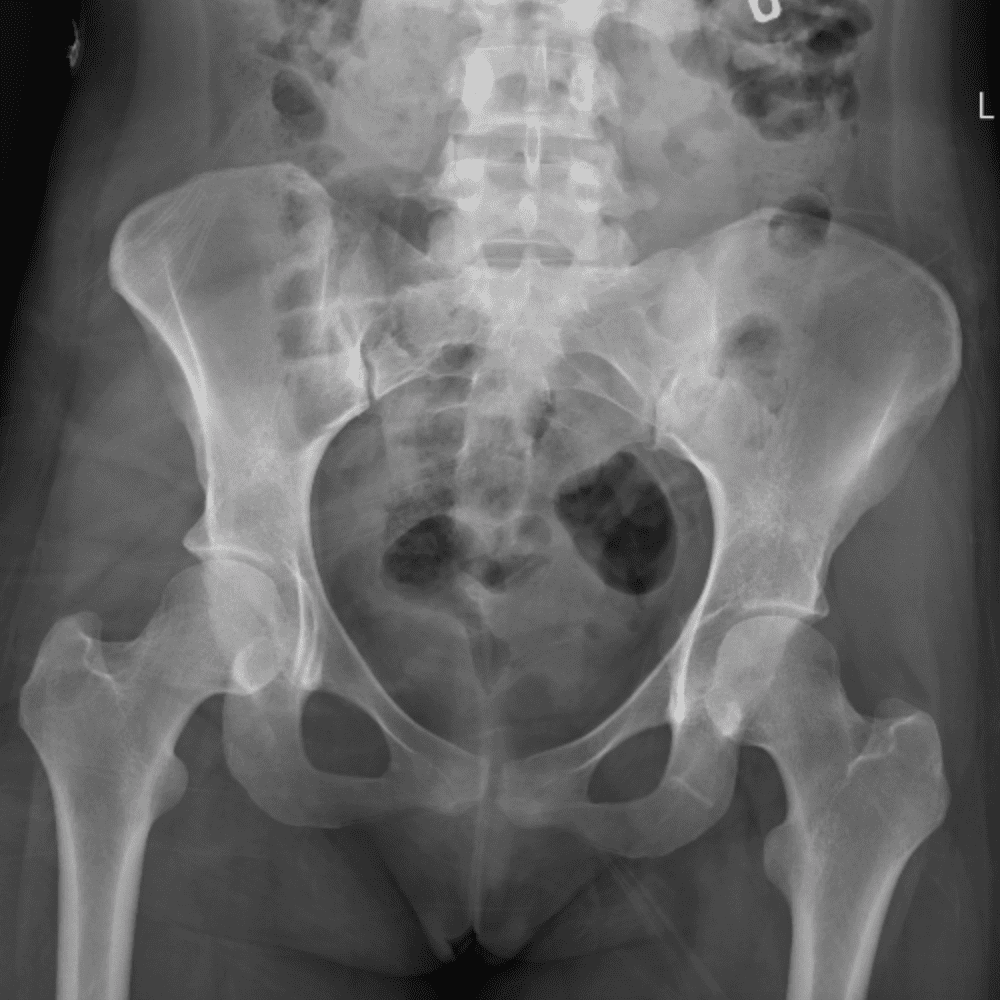

通过包含微妙或困难的病例和一些正常病例来模拟值班。